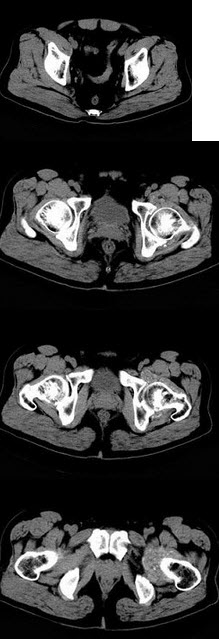

男,60岁,因双髋关节反复疼痛2年余,无明显外伤史,X线摄片如图,最可能的诊断是()

A、双髋关节退行性骨关节病

B、双髋关节创伤性关节炎

C、双髋关节特发性骨关节病

D、双髋关节结核

E、神经性关节炎